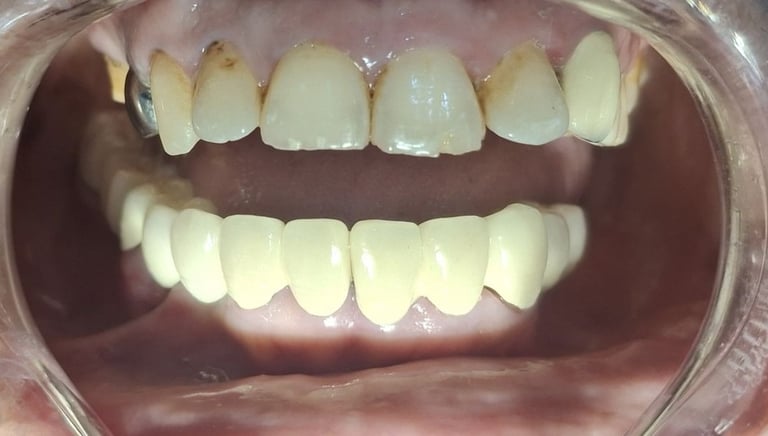

After

Before

All images shown here are real teeth cleaning cases treated at our clinic with patient consent.

Professional teeth cleaning helps remove plaque, tarter, and surface stains that regular at home brushing can not.

At Shree Dental Care, teeth cleaning is performed gently with focus on patient experience, comfort and long term oral health.